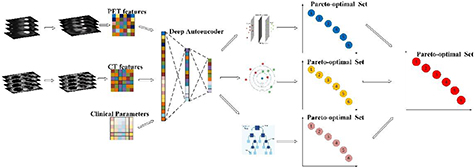

Before training and testing, a deep learning with stacked autoencoder strategy is designed to transform the features from PET, CT features as well as clinical parameters into one representation feature set in M-radiomics. We aim to generate a comprehensive Pareto-optimal model set through sorting classifier specific Pareto-optimal models in a non-dominated way in the training stage. The goal of testing stage is to fuse the non-zero weight models through analytic ER rule and get the final output probability. The problem formulation is described as follows.

The training stage of M-radiomics is shown in figure 2. Assume that the radiomic features and clinical parameters are denoted by  , where Mi represents the feature number for each modality and I is the modality number. Before training, an autoencoder model is generated using all the features from the different modalities, and the hidden layer is taken as the final feature set which is fed into the model, that is:

, where Mi represents the feature number for each modality and I is the modality number. Before training, an autoencoder model is generated using all the features from the different modalities, and the hidden layer is taken as the final feature set which is fed into the model, that is:

Figure 2. Illustration of the training stage of M-radiomics.

Standard image High-resolution imagewhere  represents stacked autoencoder and

represents stacked autoencoder and  is the feature set generated from the hidden layer in training stage. Assume that there are N base classifiers and the model parameter set for each classifier is denoted by

is the feature set generated from the hidden layer in training stage. Assume that there are N base classifiers and the model parameter set for each classifier is denoted by  . Since the feature selection influences the model performance, we perform feature selection and model training simultaneously for each base classifier which is: